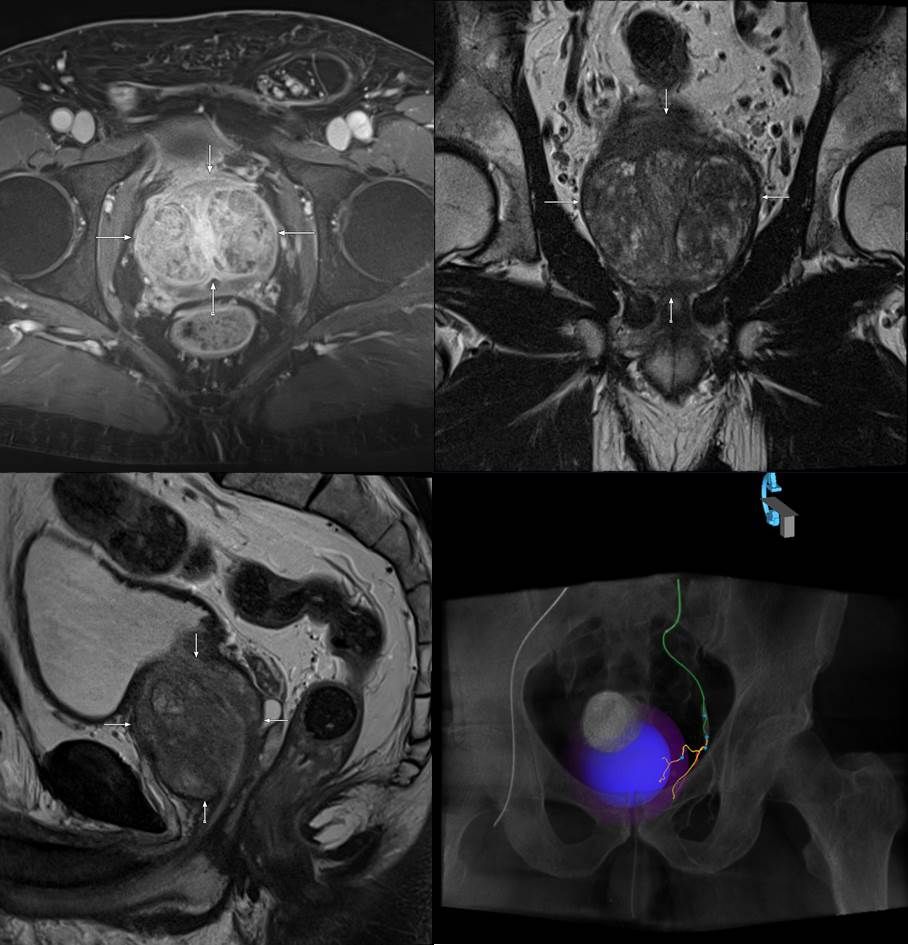

Unser Zentrum zeichnet sich weiterhin durch eine dreidimensionale bzw. räumliche periprozedurale Planung der Embolisation aus, hierbei werden die arteriellen Blutgefäße der Prostata dreidimensional im Raum dargestellt, um alle versorgenden Gefäße ausreichend und gezielt behandeln zu können, dies reduziert das Risiko einer ungewollten Embolisation anderer, benachbarter Gefäße (zum Beispiel darmversorgende Arterien).